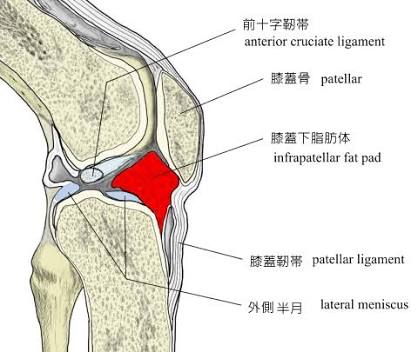

まず想像して欲しいのですが、大腿四頭筋という筋肉は腿前全体を覆って、ひざのお皿の下までついています。

そのため、ひざの関節を伸ばすと筋肉の両端が中央に向かうので、ひざのお皿も上の方向(お腹側)に向かって動きます。

ひざのお皿が上の方向に向かうに連なって、膝蓋靭帯というお皿の下についている靭帯やこの靭帯の下にある膝蓋下脂肪体や半月膝蓋靭帯も動くことで、半月板を前に引っ張ってくれています。

もし、大腿四頭筋が筋力低下していたらそれらのパーツも働かなくなるので当然、半月板も動かないです。

本来はひざの関節が伸びると半月板は前に移動することで円滑な関節運動起きるのが、ももの骨とスネの骨に挟み込まれてしまい、痛くなるという公式が出来上がってしまいます。